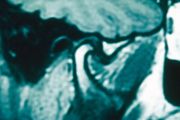

| 19:05, 16 April 2023 | MR frontal TMJ .jpg (file) |  |

1.12 MB | 1 | |